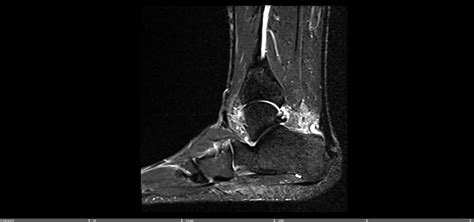

To confirm the diagnosis and rule out other potential issues, your doctor might order imaging tests. X-rays are often the first line of imaging. They’re great for visualizing bone spurs, which are common with insertional Achilles tendonitis, and can help rule out fractures or other bone abnormalities. If more detail is needed, they might recommend an ultrasound or an MRI . An ultrasound can provide real-time images of the tendon, showing inflammation, degeneration, or tears. An MRI offers a more detailed view of soft tissues, allowing the doctor to assess the extent of tendon damage and identify any other soft tissue problems in the area.